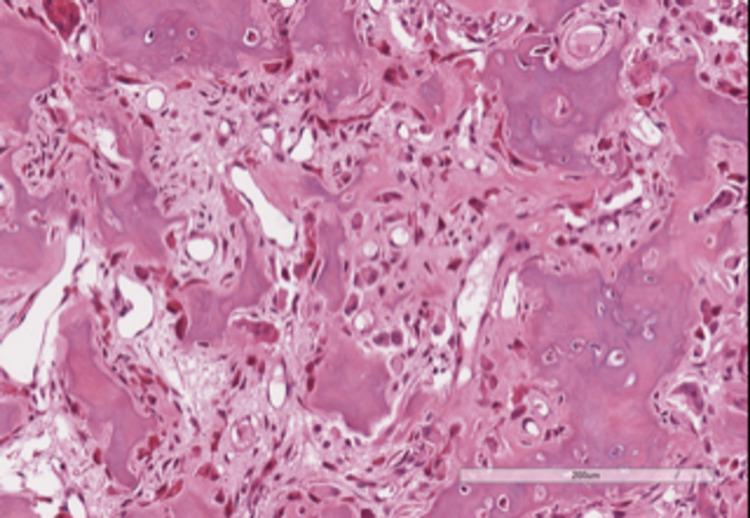

Cervical radiculopathy is a common clinical condition with an annual incidence of 85/10,000. Refractory cases with positive disco-vertebral imaging findings are routinely referred to the Neurosurgeon for evaluation and treatment. In the absence of a clearcut compressive etiology, other rarer but surgically curable causes must be considered before recommending conservative management. We discuss the case of an otherwise active, healthy patient with an invalidating, refractory, relapsing nuchal pain and cervical radiculopathy. Only careful and state-of-the-art neuroimaging led to the correct diagnosis: an osteoid osteoma of the right C6 lamina was diagnosed and microsurgically resected allowing complete recovery and cure. The clinical features of these rare tumors in this unusual location are reviewed. The case is relevant for multifold reasons: it draws attention to rare conditions which can mimic radicular compression; emphasizes the need for a careful evaluation and appreciation of specific clinical symptoms and signs associated with non-compressive radiculopathies; prompts planning of a state of the art imaging workup, in order to rule out such an elusive tumor. All these measures minimize the risk of overlooking the present and other rare pathologies, sparing patients a long path of time-consuming, frustrating and cost-ineffective studies and treatment modalities.